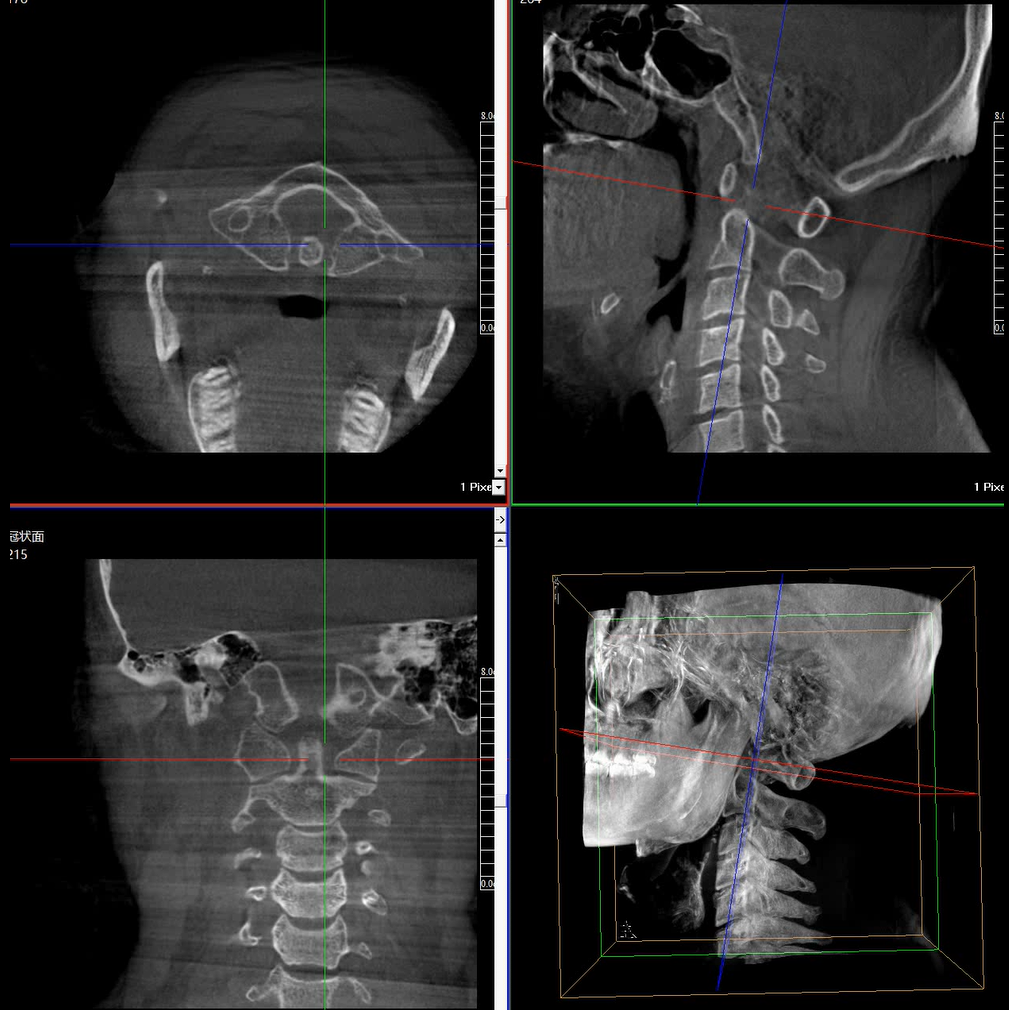

術中三維成像和橫斷面圖像提供多角度的手術診斷信息,輔助醫生進行術中評估判斷,諸如骨折復位情況和內植入螺釘的尺寸和位置,輔助手術更好地完成。

提供更大的術中三維成像視野,采集更多圖像信息,可一次拍全全段頸椎、全段腰椎、七節胸椎、雙側骶髂關節、股骨頭及單側盆骨。

在C臂掃描過程中,始終保持拍攝主體處于射線束的中心,避免了序列圖像采集過程中的橫縱方向運動,減少相對運動造成的運動偽影。